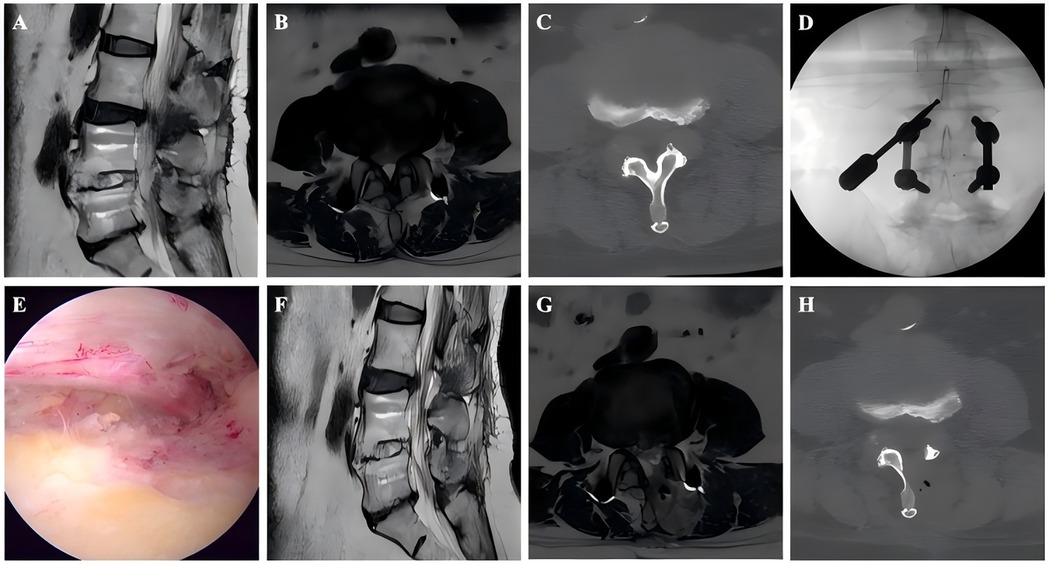

Background: Unilateral biportal endoscopy (UBE) is an important minimally invasive surgical treatment option for lumbar spinal stenosis (LSS). However, to our knowledge, no studies have focused on UBE for treating adjacent segment disease (ASD) after lumbar fusion. Thus, this study aimed to analyze the clinical efficacy of UBE for ASD patients, and further compare it with non-ASD patients. Methods: This retrospective study enrolled consecutive patients who underwent UBE decompression surgery for LSS between January 2022 and March 2024. According to the inclusion and exclusion criteria, 82 patients were divided into study group (42 ASD patients) and control group (42 non-ASD patients matched by sex, surgical level, and age). Surgical outcomes were evaluated using the visual analog scale (VAS) and Oswestry Disability Index (ODI) obtained preoperatively, 3 days postoperatively, and at 3- and 12-month follow-ups, along with the MacNab criteria, cross-sectional area of the dural sac, and incidence of complications. Results: The ASD and non-ASD groups enrolled 42 patients each. Except for the operative time (P < 0.001), no significant differences in baseline characteristics were observed between the two groups. Both groups showed significant improvement in VAS scores, ODI scores, and dural sac cross-sectional area after UBE surgery (P < 0.001), with sustained clinical efficacy throughout the follow-up period. Although the ASD group had significantly higher preoperative VAS scores for back pain than the non-ASD group (4.78 ± 1.41 vs 4.02 ± 1.65, P = 0.027), no significant differences were found between the groups at any postoperative follow-up (3 days, 3 months, or 12 months). Based on the MacNab criteria, excellent or good outcomes were observed in 85.7% (36/42) of the patients in the ASD group and 88.1% (37/42) in the non-ASD group, with no significant difference. The incidence of complications was comparable between the two groups (P = 1.000), and no severe complications were observed. Conclusion: UBE demonstrated favorable clinical outcomes and safety in treating ASD patients. It may represent a promising minimally invasive option for elderly patients with multiple comorbidities who cannot tolerate revision surgery.